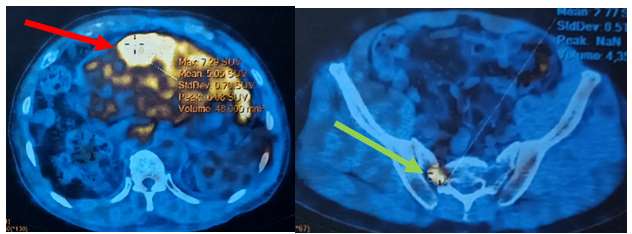

- Bệnh nhân được chụp PET/CT (Positron Emission Tomography and Computed Tomography hay chụp cắt lớp ghi hình positron.

Hình 6: Hình ảnh chụp PET/CT: Hình ảnh khối ở gan hạ phân thùy III kích thước 36x66x71mm, tăng chuyển hóa FDG (SUV max= 7,3) (bình thường nhỏ hơn 2,5) (mũi tên đỏ) (FDG là một dược chất phóng xạ dùng trong chụp cắt lớp ghi hình positron, SUV max là giá trị hấp thu tiểu chuẩn tối đa FDG, tăng cao chuyển hóa FDG hướng tới gợi ý tổn thương ác tính). Không phát hiện hình ảnh tăng chuyển hóa FDG tại vị trí gan phải (tổn thương u gan cũ đã SIRT). Hình ảnh tăng chuyển hóa FDG tại cánh xương cùng, nghĩ đến do di căn (SUV max= 4,5) (mũi tên xanh).

Hình 7: Hình ảnh chụp PET/CT: Không thấy hình ảnh tăng chuyển hóa FDG tại vùng thái dương chẩm trái (vị trí đã phẫu thuật ung thư hắc tố ác tính).